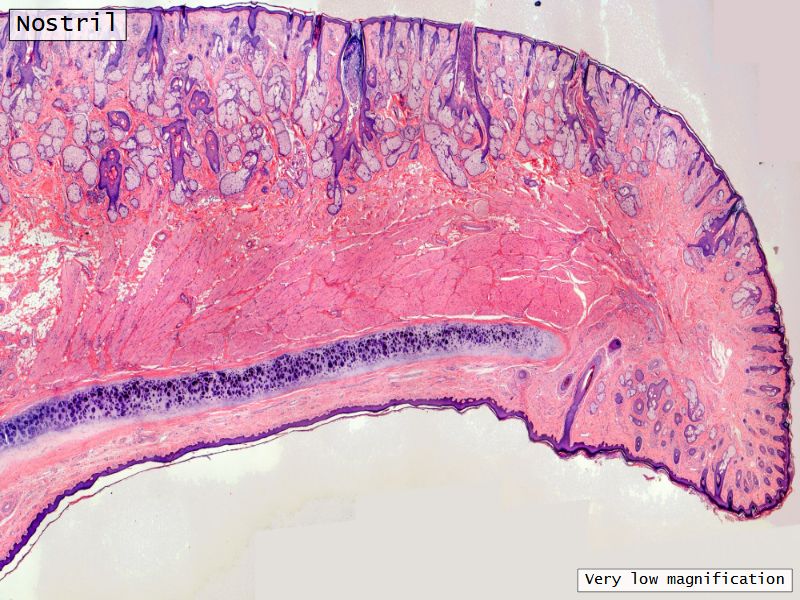

Fill in all the missing labels, and assess as you move through the slides. Answers on the down slide. It is important to do this using pen and paper, and not just glance through the images.